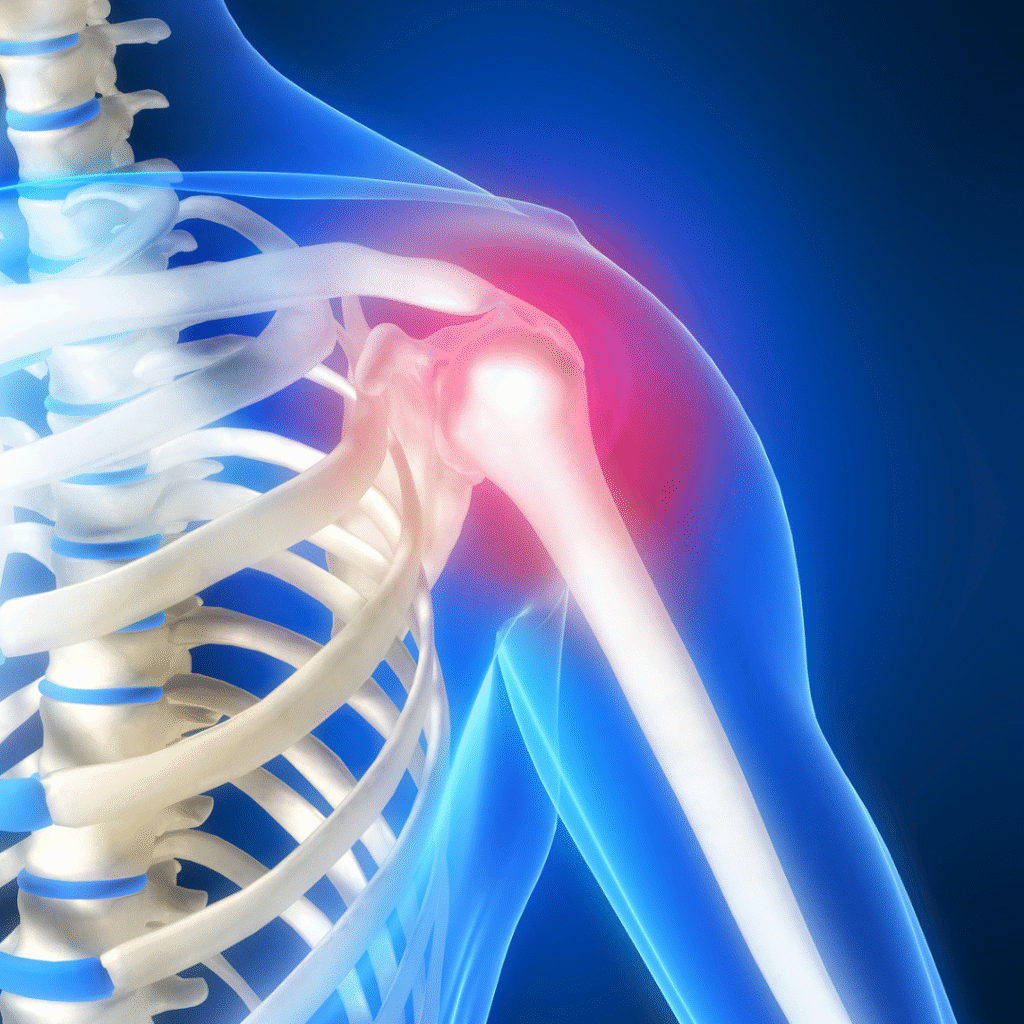

Shoulder injuries can significantly impact your ability to move, work, and live comfortably. At our orthopedic practice, our shoulder specialists are dedicated to diagnosing and treating a full range of shoulder conditions—from rotator cuff tears and labral injuries to arthritis and instability. Whether you’re dealing with a sports-related injury or chronic shoulder pain, we combine advanced techniques with personalized care to help restore function, reduce pain, and get you back to doing what you love.